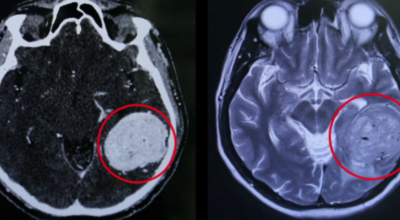

뇌종양이란 뇌 조직이나 뇌를 싸고 있는 막에서 발생한 종양과, 머리뼈나 주변 구조물로부터 멀리 떨어진 부위에서 뇌 조직이나 뇌막으로 전이된 종양을 의미해요. 뇌종양은 양성과 악성으로 나눌 수 있습니다. 양성 뇌종양은 성장 속도가 느리며 주위 조직과의 경계가 뚜렷해요. 양성 뇌종양은 수술 이외의 다른 치료 없이 완치되는 경우가 흔하고, 대부분 천천히 자라기 때문에 수술하지 않고 경과를 관찰하기도 해요. 그러나 양성 뇌종양도 완치될 수 없는 경우가 있습니다.

뇌간이나 척수와 같은 특정 부위에 발생된 종양은 수술로 없앨 수 없습니다. 또 크기가 작더라도 생명에 중요시되는 기능을 담당하는 뇌와 척수에 정도가 심한 훼손을 입힐 수 있답니다. 이 경우 조직학적으로는 양성이지만, 임상적으로는 악성과 같습니다. 악성 뇌종양은 뇌암이라고도 하고, 성장 속도가 빠르며 주위 조직으로의 침투 역량이 강해요. 이에 따라 정상 뇌 조직으로 침윤되고 정상 뇌 조직과의 경계가 불분명해서 치료가 어려운 편이예요. 악성 뇌종양은 주변의 정상 뇌 조직을 빠른 속도로 파괴해요.